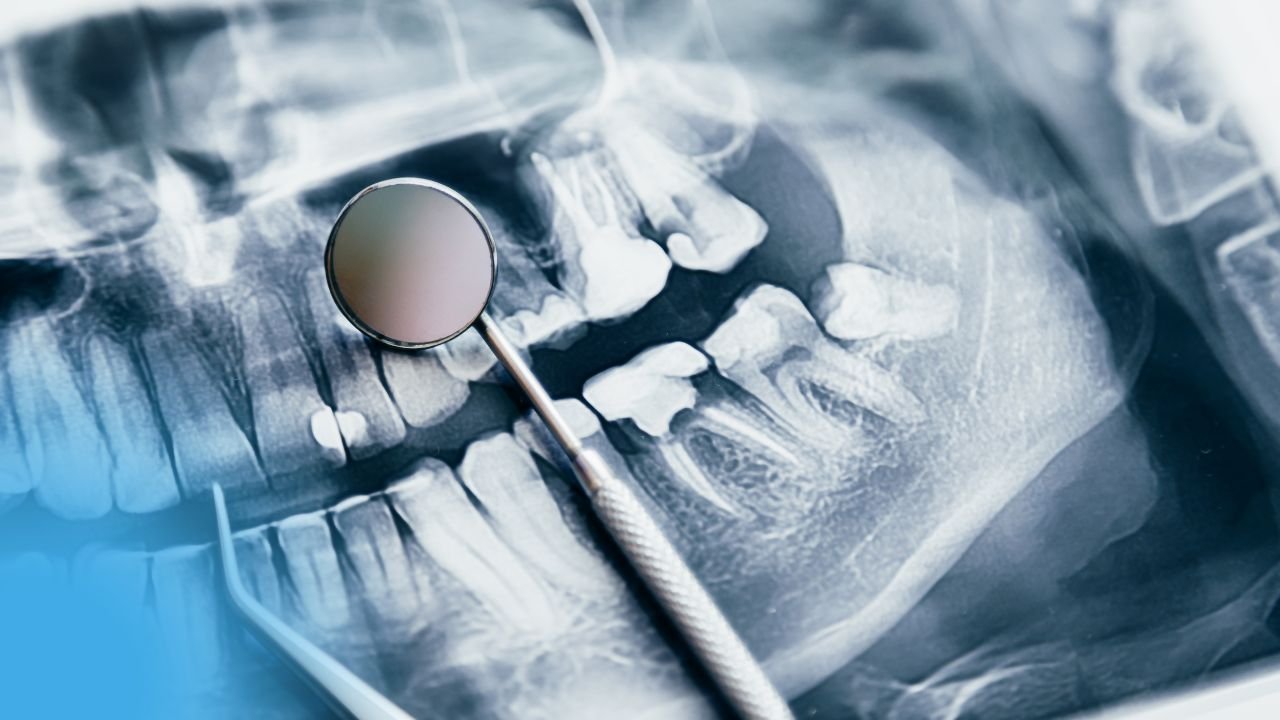

Lire l'articleClassification et formes cliniques des maladies parodontales; Parodontologie Introduction Les maladies parodontales sont des maladies multifactorielles en raison de leurs...

Lire l'articleÉtiologie des Maladies Parodontales; Parodontologie Introduction En médecine, l’étiologie est l’étude des causes et des facteurs d’une maladie. L’étiologie des...

Lire l'articleL’Étiologie des Maladies Parodontales, Parodontologie Introduction Par définition, l’étiologie est la science des causes ou des origines. Les facteurs étiologiques...